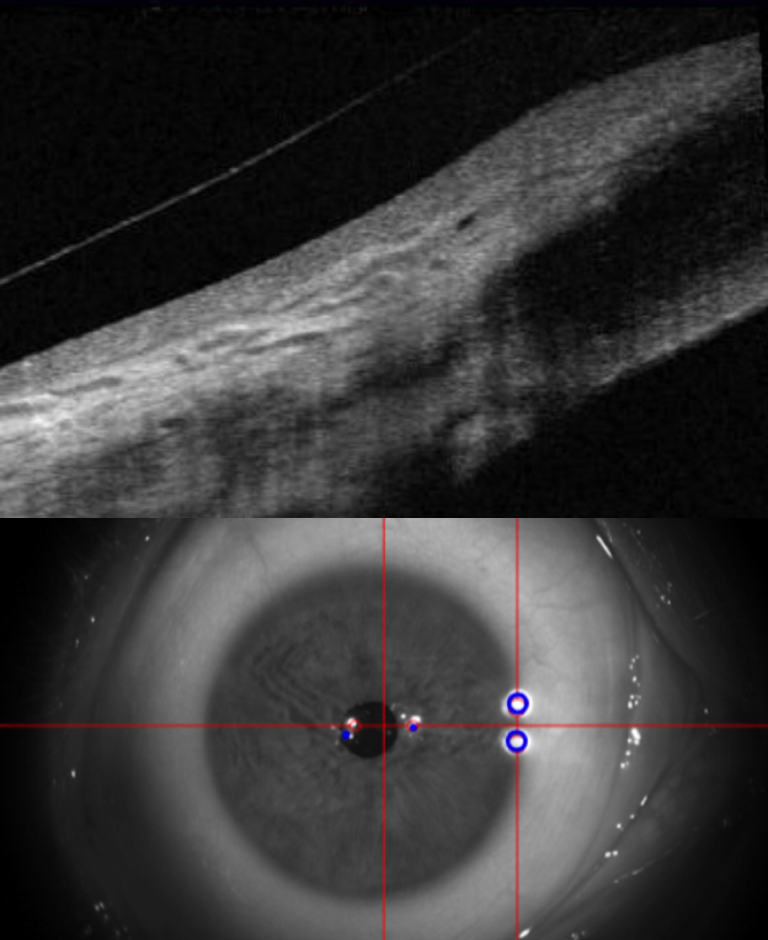

A close up eye with crosshairs

Bespoke Fitting

State-of-the-art imaging and specialist expertise

At Park Vision, scleral lenses are fitted by fully trained optometrists with specialist expertise in advanced contact lens care. We use state-of-the-art imaging and detailed scleral profiling technology to accurately map the shape of your eye, allowing each lens to be precisely customised for an optimal fit.